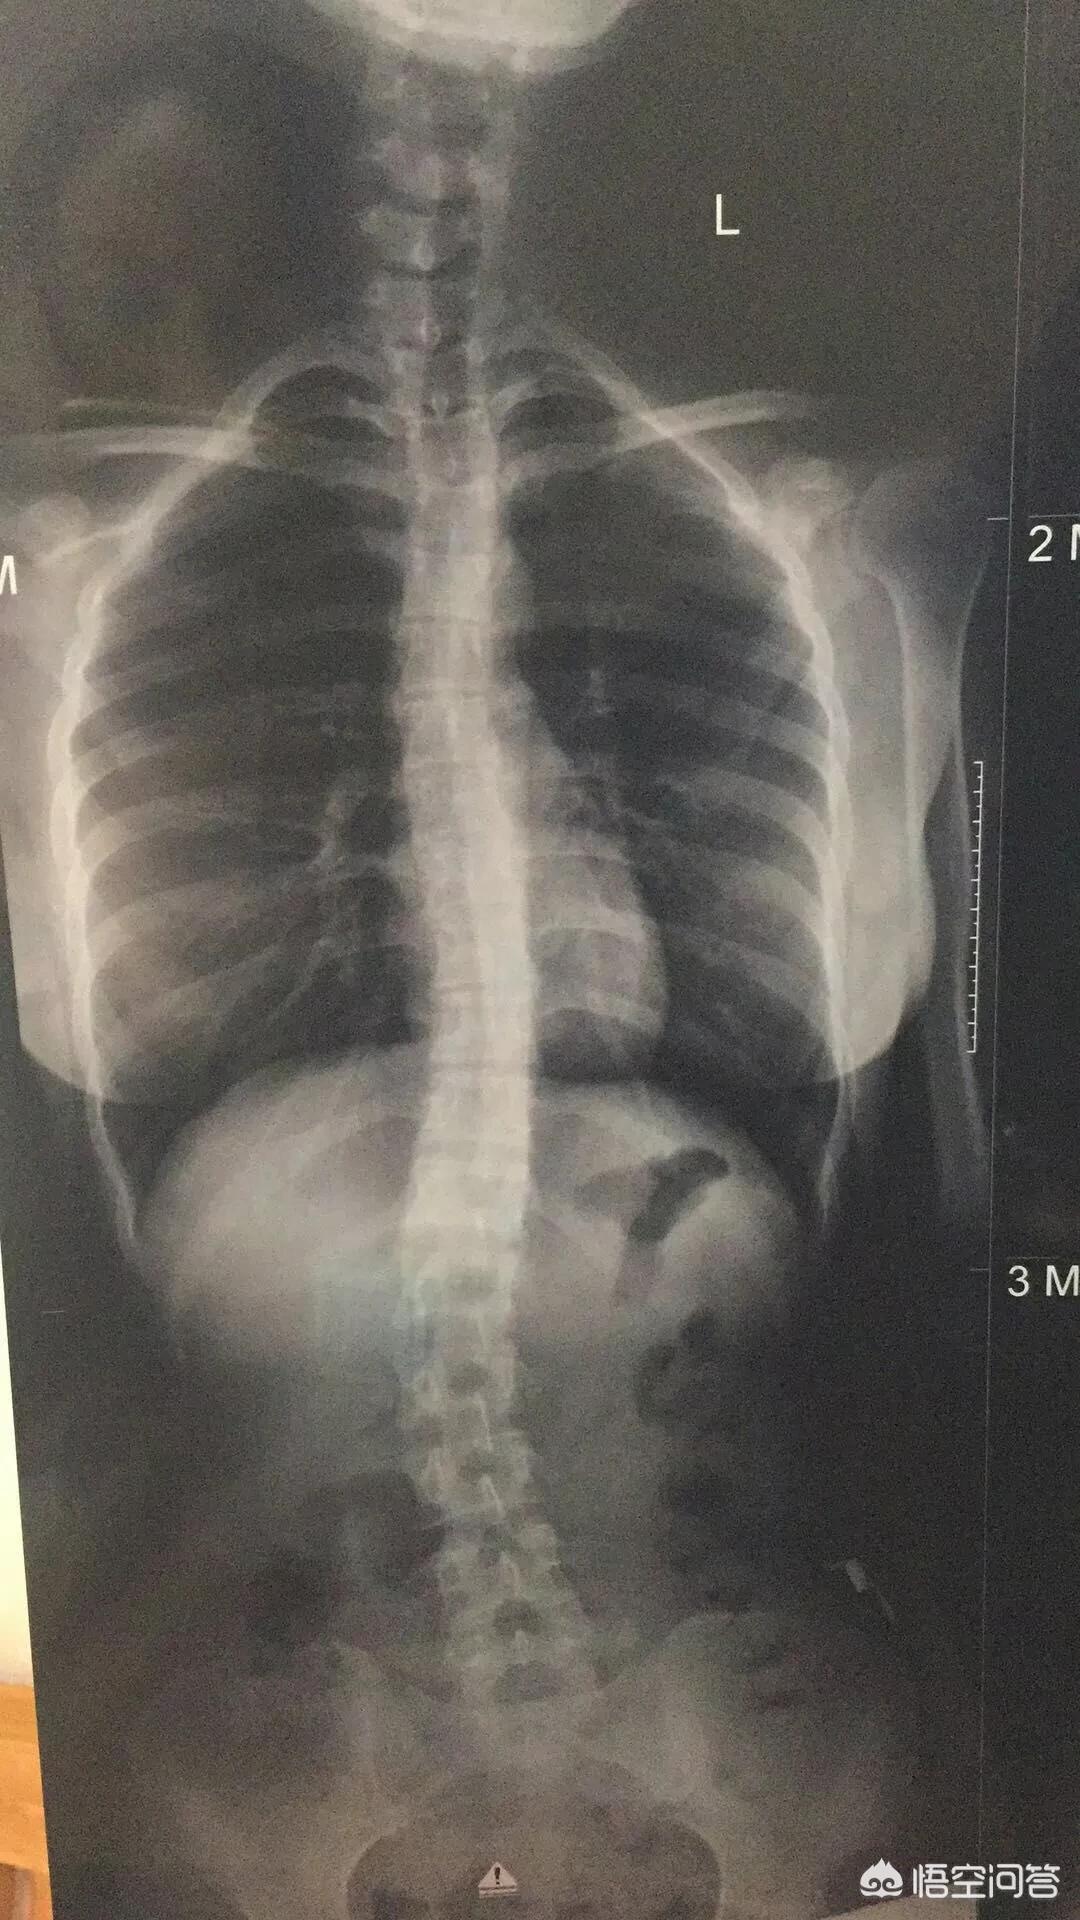

从专业上讲叫脊柱侧凸,是指脊柱在冠状位、矢状位出现失衡引起的一个畸形,脊柱侧弯往往是在通过X线表现冠状位超过10度,就被诊断为脊柱侧弯,轻度的脊柱侧弯小于10度以上的,或者20度以上的脊柱侧弯,会带来外观上的一些改变,如果是大于40度以上的脊柱侧弯,往往会带来明显的一个外观改变,严重的会影响到脊柱内的脊髓、神经功能,进而引起临床症状,因此轻度的脊柱侧弯可以选择观察,严重的脊柱侧弯往往是选择需要手术治疗。

2,代偿性脊柱侧弯,就是指没有先天性椎体发育缺陷,但在后天生长中,太多的不良习惯,而出现脊柱侧弯,通常角度不大,但患者有明显的疼痛不适,80%的患者多发于快速生长的青春期。

而在中国,因为青春期时正是教育压力最大的时期,久坐学习时间过长,也是我国青少年脊柱侧弯高发的主因。

在深圳某高中抽查时,就发现过70%的少年存在不同程度的脊柱侧弯,可以说已经是仅次于近视的第二大青少年健康问题。

第二、根据严重程度来分类。分为轻度、中度、重度以及极重度。Cobb角在40度到80度之间为中度的脊柱侧弯,Cobb角大于80度的往往是重度脊柱侧弯。小于40度的轻度脊柱侧弯可以通过保守治疗,例如支具、体育运动锻炼等等。40度到80度之间的中度脊柱侧弯,通过支具是没有太大的效果,有可能会影响到患者的心肺功能,需要考虑手术治疗。